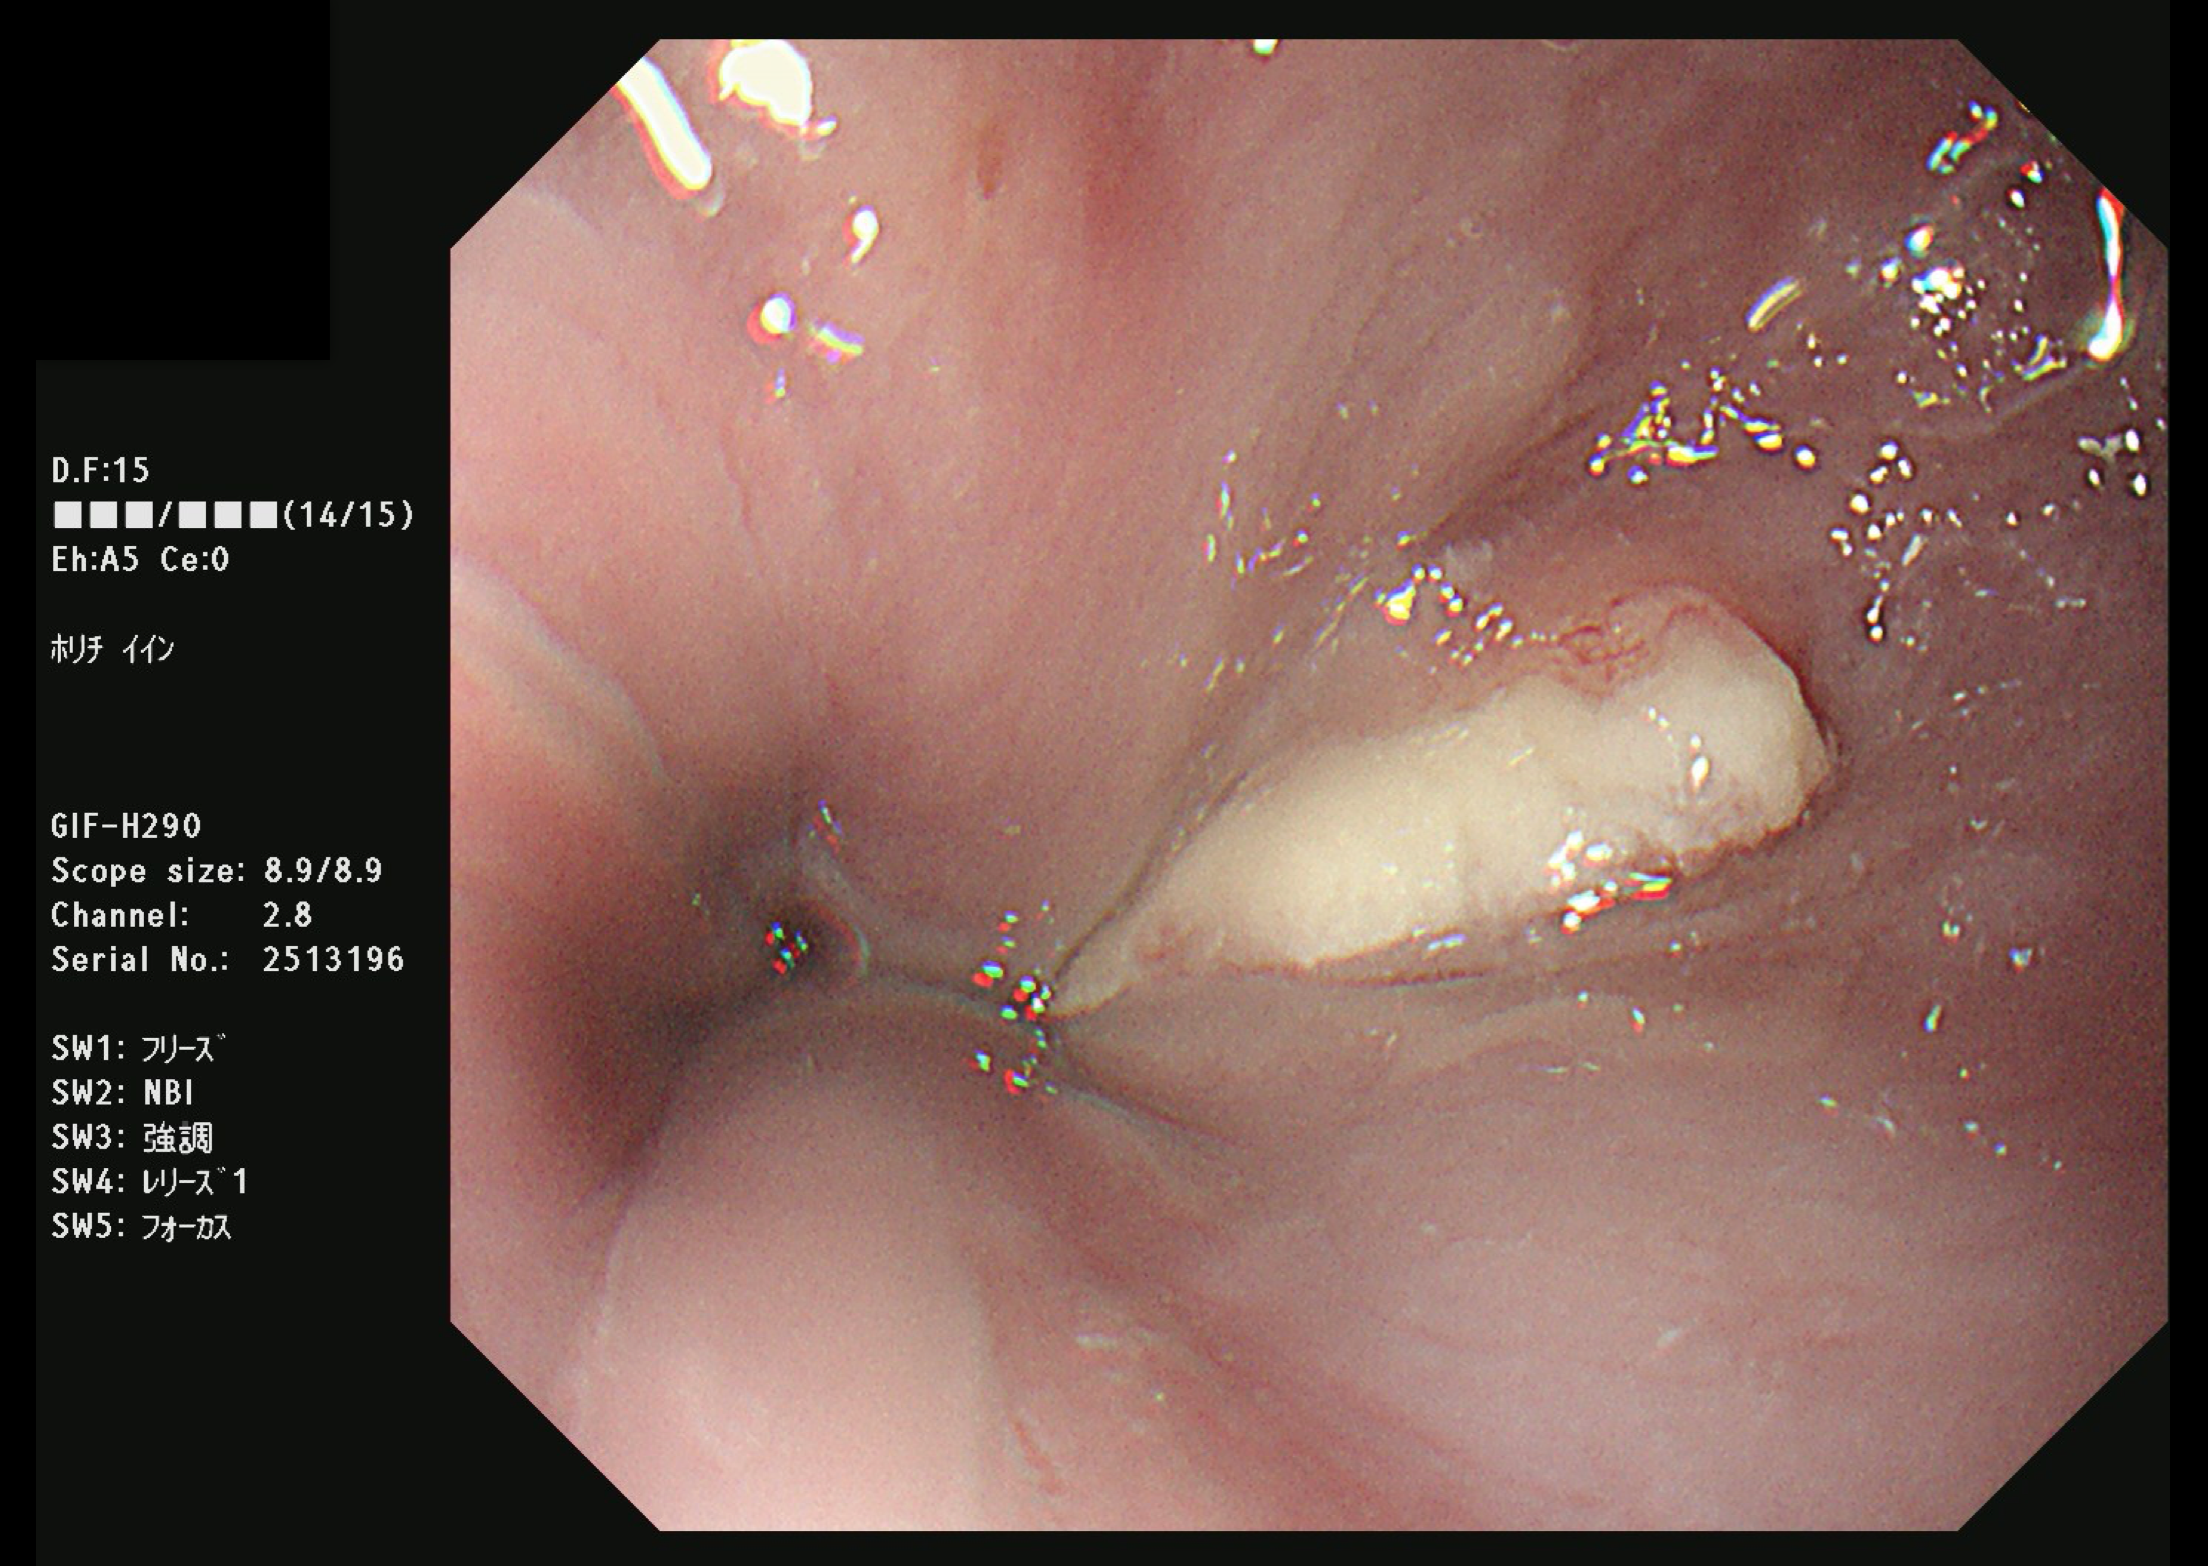

胃がん(上部消化管内視鏡)

食道がん(上部消化管内視鏡)

富山市の胃がん検診は胃内視鏡(上部消化管内視鏡)もしくは胃透視(バリウムを飲む検査)でおこなわれています。胃がんはかつては日本人にとって非常に多いがんでしたが、ヘリコバクターの保菌者の減少とともに、胃がんも少なくなりつつあります。

胃がん検診では喉頭部・食道・十二指腸上部を観察します。

当院では胃内視鏡(経口)のみを実施しております。胃の中を十分に検査するために高解像度の内視鏡を使用しており、そのため口からの内視鏡検査となります。一般的に鼻からの経鼻内視鏡による検査の方が楽な検査と言われていますが、内視鏡が細い分、最新型の経口高解像度内視鏡に比べて解像度が落ちます。